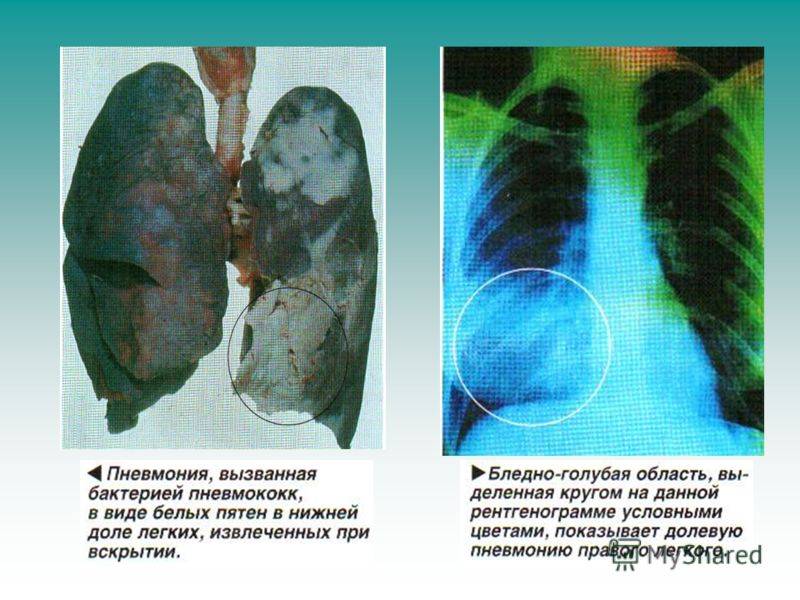

Фотографии бактерий, вызывающих бактериальные пневмонии у животных

Раздел: Другие животные